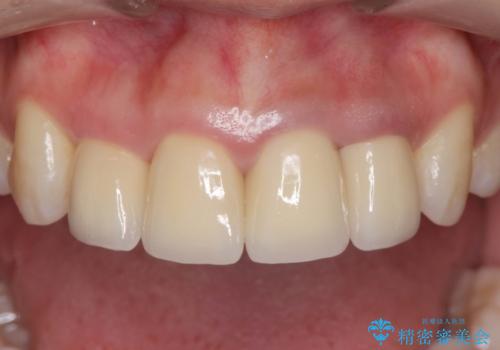

変色した歯を改善、セラミック治療

自然な歯の色に仕上げることができ、大変喜んでいただくことができました。